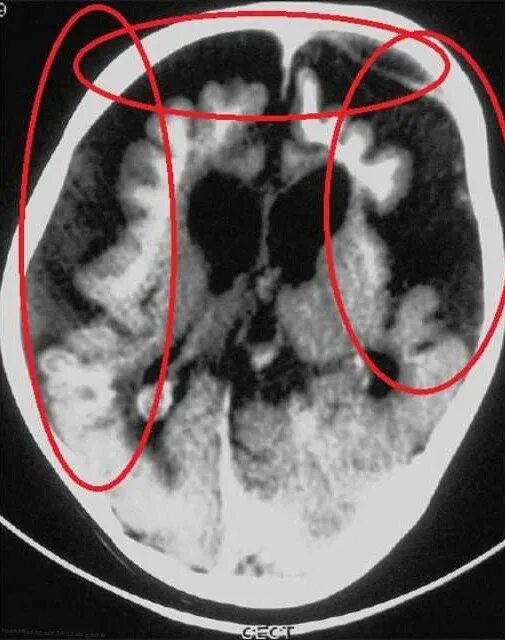

Диффузной биполушарной кортикальной атрофии